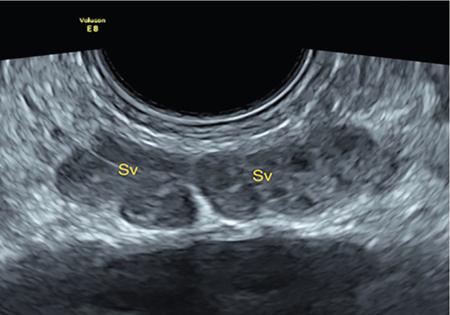

IMAGING ANATOMY OF MALE REPRODUCTIVE SYSTEM Ganesh Rajagopal The male reproductive system is formed by testes, ejaculatory ducts, seminal vesicles (SVs), prostate and penis. Various diagnostic imaging modalities like ultrasound (US), computed tomography (CT), magnetic resonance imaging (MRI) and positron emission tomography (PET) are helpful in the diagnostic evaluation of male reproductive system. Various indications for imaging may include acute scrotum (testicular torsion, trauma and epididymo-orchitis), scrotal swelling (hydrocele, spermatocele, idiopathic scrotal wall oedema and scrotal abscess) and infertility. US and MRI are the commonly used imaging modalities in male reproductive system which complement each other. CT is not very useful due to poor contrast resolution. Ultrasound imaging (US) with a high-frequency linear (7.5–10 MHz) transducer probe has become the imaging modality of choice for scrotal evaluation. Scrotal US is an excellent imaging modality as it can demonstrate abnormalities in testis as well as in paratesticular structures. Scrotal wall is formed by the skin, superficial fascia, dartos muscle, the external spermatic fascia, cremasteric fascia and the internal spermatic fascia. The scrotum is divided into two cavities by a median raphe. This multilayered scrotal wall is poorly delineated in US and MRI, it is typically hypointense on both T1- and T2-weighted images. Testes are paired organs, located normally in scrotal sac, suspended by the spermatic cords. Each testis is examined in orthogonal transverse and longitudinal planes, with both grey scale and colour Doppler modes, to assess its volume and blood flow. Volume of testis is calculated by length × height × width × 0.71. A total volume (both testes) of >30 mL and a single testicular volume of 12–15 mL is generally considered normal for adults. Testes are supplied by the testicular arteries, which arise from the aorta and enter the spermatic cord at deep inguinal ring to reach the upper pole of testis. Pampiniform plexus of veins surrounds the testis and appears as a serpiginous tubular structure posterior to it, measuring >2–3 mm in diameter. Testes are oval shaped, with homogeneous echotexture on grey scale US. Along with the epididymis, they are surrounded by an echogenic capsule, known as the tunica albuginea. Tunica albuginea is covered by tunica vaginalis, which is a remnant of the processus vaginalis and both represent closed sac of peritoneum with two layers. This tunica albuginea is seen extending into posteromedial testis and form the mediastinum testis (Fig. 11.2.1.1), which consists of ducts, nerves and blood vessels. The mediastinum testis is seen as a thin echogenic band. Rete testis is formed by the convergence of seminiferous tubules, seen as a hypoechoic area adjacent to mediastinum testes. The epididymis is a comma-shaped, elongated structure placed at the posterior border of the testis, which drains the efferent ductules (Fig. 11.2.1.2). It has head, body and tail. The head overlies the superior pole of the testis and is isoechoic or slightly hyperechoic whereas, the body and tail are located behind and along the inferior pole and are usually isoechoic. The tail of the epididymis continues into vas deferens (VD), which along with the nerves, lymphatic and vascular structures, forms the spermatic cord (Fig. 11.2.1.3). The spermatic cord appears as an echogenic band in the inguinal canal. The normal adult testis is a homogeneous oval structure that appears hyperintense on T2-weighted sequences and hypointense–isointense on T1-weighted images (Fig. 11.2.1.4). The tunica which surrounds the testis is hypointense T1- and T2-weighted sequences. Epididymis is isointense on T1-weighted images but hypointense on T2-weighted images compared to testis (Fig. 11.2.1.5). Both testicles and epididymis enhance after intravenous administration of gadolinium (Gd) MR contrast agents. Prostate, though visualized by transabdominal scan is better assessed by transrectal high frequency (7.5–10 MHz) ultrasound transducer (TRUS) with patient in left lateral decubitus position. The prostate gland is divided into the anterior fibromuscular stroma (devoid of glandular tissue), transition zone, central zone, periurethral zone and peripheral zone. The base of the prostate is located superiorly and contiguous with the bladder neck whereas, the apex of the prostate is located at the inferior aspect continuous with the striated muscles of the urethral sphincter. The neurovascular bundle is seen to course near the posterolateral aspect of prostate, which is a preferential route of tumour spread. The prostate appears as a cone-shaped organ and shows uniform low echogenicity (Fig. 11.2.1.6). The outer gland (central and peripheral zones) is generally more echogenic than the inner gland. The transition and central zones of the prostate have similar MR signal intensity and cannot be differentiated, hence, are collectively referred as the central gland. On T2-weighted MR images, the normal peripheral zone is homogeneously hyperintense, whereas the central gland tissue is typically hypointense or isointense compared to the skeletal muscle (Fig. 11.2.1.7). The capsule and the anterior fibromuscular stroma appear hypointense on T2-weighted MR images. The SVs are seen as septate tubular cystic structures, appearing uniformly anechoic in US, above the prostate with distal portion of VD is seen medial to it. The duct of SV and VD joins to form the ejaculatory duct, which drains into the prostatic urethra via verumontanum. SVs show ‘bow-tie’ appearance in transversal scans, and a club or tennis-racket shape in longitudinal scans (Fig. 11.2.1.8). On MR, SVs are seen as elongated fluid-containing structures with thin septa, which is hypointense on T1 and hyperintense on T2-weighted MR images (Fig. 11.2.1.9). The VD is seen as a tubular structure with low signal intensity in both T1- and T2-weighted images, on either side. The dilated distal portion of VD (ampulla), appears hyperintense on T2-weighted images, similar to that of the SV due to the fluid content (Fig. 11.2.1.10). The penis, being a superficial organ, is usually examined with US, although MRI is reserved as problem solving modality. The penile body contains two paired muscles – corpora cavernosa and a corpus spongiosum. The former performs as a main erectile body while the latter contains the penile urethra (Fig. 11.2.1.11). Dartos fascia forms the outer layer and the Buck fascia forms the inner layer, which contain the deep dorsal vein (DDV) and a paired dorsal neurovascular bundle. The corpus spongiosum and corpora cavernosa are of high signal intensities on T2-weighted MR images and intermediate-low signals on T1-weighted MR images. The tunica albuginea being a fibrous sheath, surrounds all the three muscles, is hypointense on all sequences (Fig. 11.2.1.12). IMAGING ANATOMY OF FEMALE REPRODUCTIVE SYSTEM Saranya The female reproductive system comprises of uterus, cervix, fallopian tubes, ovaries, vagina and vulva. Ultrasonography (transabdominal and transvaginal) is the primary imaging modality of choice for imaging the female pelvis. Computed tomography (CT) is less often used for pelvic imaging. It provides a quick and systematic overview with coverage of the abdomen in the same session. Hence, CT is well suited for staging pelvic cancers and for imaging gynaecologic and nongynaecologic diseases presenting with acute abdominal pain. Pelvic anatomy is well demonstrated by magnetic resonance imaging (MRI). The contrast resolution of T2-weighted images form the basis for superb tissue characterization of MRI. Uterus is a thick-walled fibromuscular organ composed of myometrium and endometrium. It has two major divisions, namely, the body (corpus) and cervix. The fundus lies above the ostia of fallopian tubes. The normal uterus measures between 5 and 9 cm in length and is in an anteverted position, in relation to the urinary bladder. The myometrium shows three layers on USG, a compacted thin, hypoechoic inner layer forms subendometrial halo, a thicker, homogenously echogenic middle layer and a thinner, hypoechoic outer layer (peripheral to arcuate vessels). The appearance of the endometrium varies with the phase of the menstrual cycle. It appears as a thin echogenic line early in the proliferative phase and shows hypoechoic thickening (4–8 mm) as proliferative phase progresses. It shows a triple layer (sandwich or trilaminar) appearance in the mid cycle and may measure up to 12–16 mm. During secretory phase after ovulation, the layers are seen hyperechoic due to the increasing complexity of glandular structure and secretions (Fig. 11.2.2.1). Postmenopausally, the endometrium decreases in thickness. Endometrial thickness of 5 mm is taken as cut-off. Women on hormonal therapy acceptable endometrial thickness is up to 8 mm. Three-dimensional US permits multiple views to be reconstructed from a single sweep through the uterus. Sonohysterogram is the study of choice for detailed evaluation of the endometrial cavity pathologies. The cervix begins at the inferior narrowing of the uterus (isthmus) at the internal os, which is identified by the entrance of uterine vessels. It has supravaginal and vaginal portions. It is 3–4 cm long and shortens after childbirth. In premenarche women, cervix is larger than corpus, forming approximately 2/3 of the uterine mass. During menarche, there is preferential growth of the corpus and in nulliparous women, corpus and cervix are roughly equal, whereas in parous woman, corpus forms approximately 2/3 of the uterine mass. Uterus is an extraperitoneal organ. The peritoneum extends over urinary bladder dome to anterior uterus, forming anterior cul-de-sac (vesicouterine pouch) and posteriorly, the peritoneum extends more inferiorly to the upper portion of vagina, forming the posterior cul-de-sac (pouch of Douglas, rectouterine pouch), which forms the most dependent portion of the female pelvis. Supporting ligaments of the uterus comprise mainly of broad ligaments, which extend laterally to the pelvic wall and round ligaments, which arise from uterine cornu near fallopian tubes to course anteriorly, pass through the inguinal canal to insert on the labia majora. Connective tissue thickening at the base of the broad ligament forms the uterosacral ligaments posteriorly, cardinal ligaments laterally and vesicouterine ligaments anteriorly. CT examination displays the uterus as a triangular or ovoid soft tissue structure behind the urinary bladder (Fig. 11.2.2.2). Following the administration of intravenous contrast, there is enhancement of myometrium that helps to delineate the endometrium. The vagina, cervix and corpus can be differentiated by morphological characteristics and enhancement pattern. The uterine corpus is typically triangular, whereas cervix is more rounded. The vagina has an appearance of flat rectangle at the level of fornix. The broad ligament and round ligaments are seen coursing laterally and anteriorly, respectively. The main source of vascular supply to uterus is from the uterine arteries. The uterine arteries pass within the broad ligament to enter the uterus, adjacent to the lateral fornices. The uterine artery passes over the ureter at the level of the cervix. Then it courses superiorly, along the lateral margin of the uterus and anastomoses with the ovarian artery. Uterine arteries give rise to arcuate arteries, which run in the outer third of myometrium. Radial arteries extend through the myometrium, which terminate as spiral arteries in the endometrium. The venous system parallels the arterial system, forms a complex venous network in the parametrium and drains to the iliac veins. Middle and lower thirds of the uterus are drained by obturator, parametrial and paracervical lymph nodes. Lymphatic drainage from the upper corpus and fundus goes to the common iliac and paraaortic lymph nodes. MRI provides a more comprehensive view of the uterine anatomy. On MRI, the uterus and cervix show uniform low to intermediate signal on T1-weighted images. On T2-weighted images, uterus shows three distinct zones, namely high signal endometrium, low signal junctional zone and intermediate signal myometrium (Fig. 11.2.2.3). The normal thickness of the junctional zone varies from 2 to 8 mm. A thickness of 9 to 12 mm is equivocal and greater than 12 mm is abnormal. Both endometrium and junctional zone become thin with oral contraceptive intake. Endometrial atrophies and the junctional zone is absent in postmenopausal women. The endocervical canal shows high signal on T2-weighted images, whereas cervical stroma shows low signal, contiguous with the junctional zone. An outer layer of intermediate signal smooth muscle is present. Nabothian cysts representing obstructed, mucous secreting glands are commonly seen as low signal on T1-weighted images and high signal on T2-weighted images. Parametrium shows low to intermediate signal intensity on T1-weighted images and variable signal intensity on T2-weighted images. The round ligaments and uterosacral ligaments show low signal intensity, cardinal ligaments and associated venous plexuses show high signal intensity on T2-weighted images. Ovaries are located posterolateral to the body of the uterus between the uterus and the pelvic sidewall. The internal iliac vessels lie immediately posterior to the ovary. Exact position is variable due to the laxity in the ligaments, parity, uterine size and position. On USG, medulla of the ovaries is mildly hyperechoic compared to the hypoechoic cortex. Developing follicles appear anechoic (Fig. 11.2.2.4). Corpus luteum may have a thick, echogenic ring and haemorrhage is common.